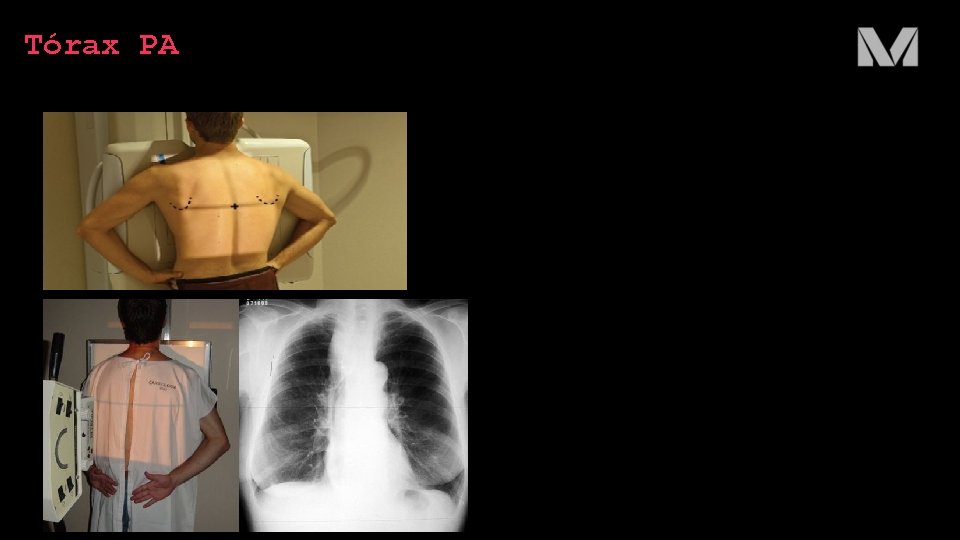

Técnica radiográfica TÓRAX PA • Tórax anterior contra o receptor de imagens para minimizar o aumento da área cardíaca • Cabeça posicionada e queixo elevado • Dorso das mãos apoiadas sobre os quadris e cotovelos girados anteriormente para movimentar as escápulas lateralmente • Ombros rebaixados, projetando as clavículas para abaixo dos ápices • Feixe central de raios X deve estar perpendicular ao receptor e centralizado ao nível da 7ª vértebra torácica (nível do ângulo inferior das escápulas) • Colimação do feixe de incluir os quatro lados campos pulmonares, a proeminência vertebral e a porção externa do tórax

Tórax PA